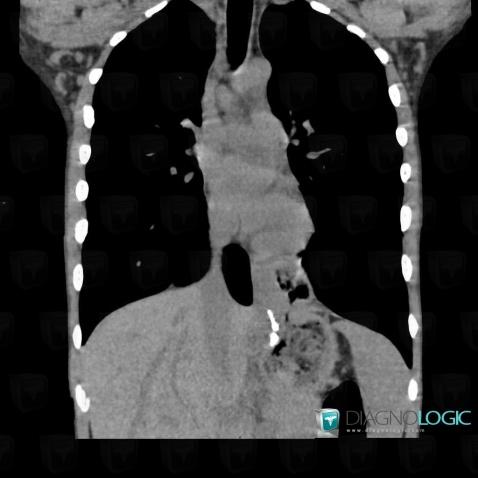

Hiatal hernia, Mediastinum, CT

Here is the specific information in the key image above:

- Diagnosis Hiatal hernia, Location(s) Mediastinum, with gamuts Posterior mediastinal mass